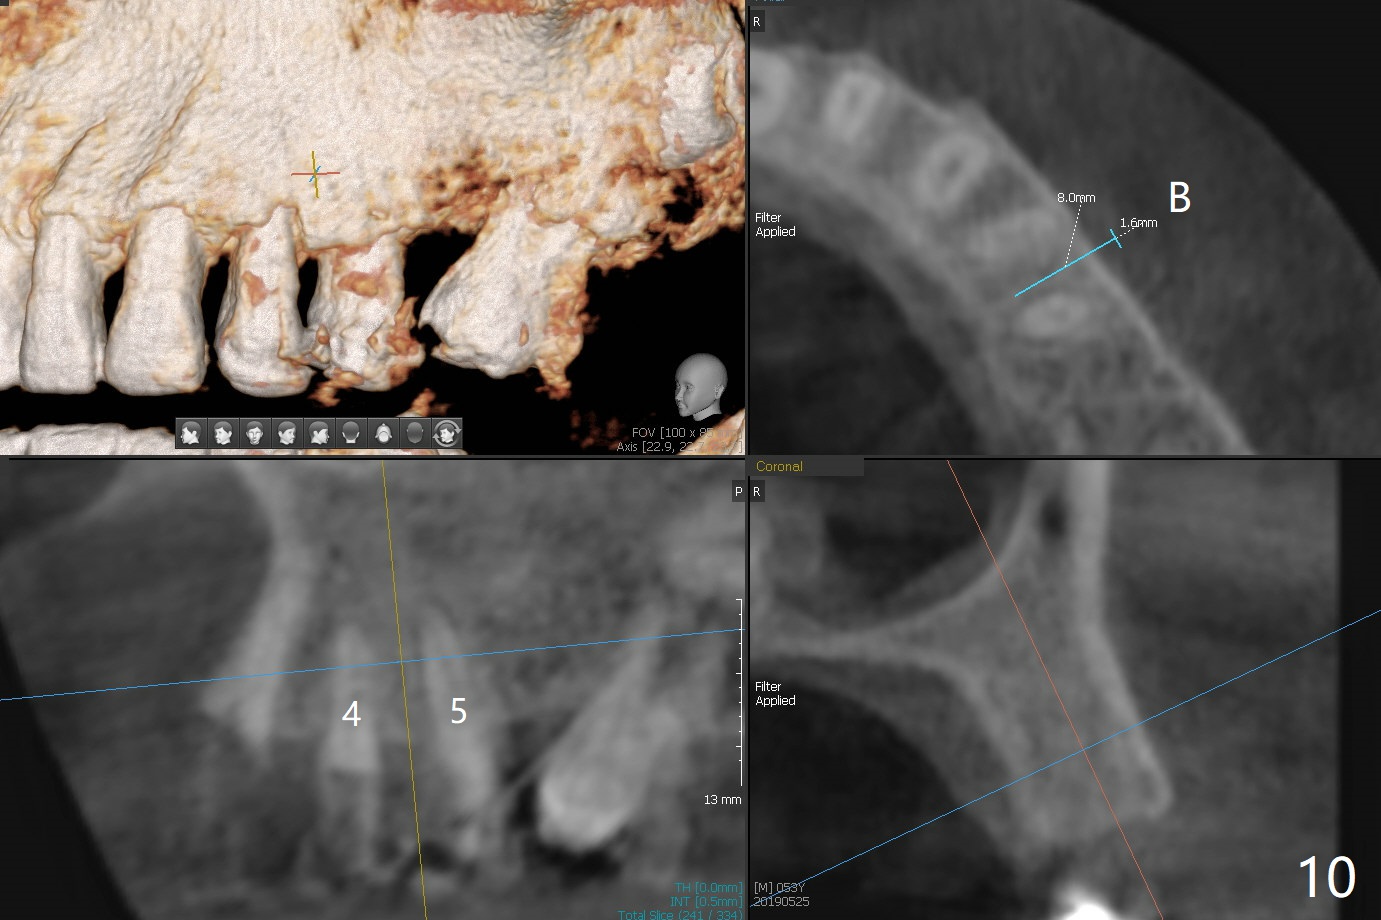

A 54-year-old man returns to office for UL7 upright 6 months post UR5 implant crown cementation (Fig.5,6). The ultimate purpose is to place implants at UL6 and LL 7. The latter will reduce severe occlusal wear especially in the lower anterior teeth (Fig.3,4). To solve the diastema between UR3 and 4 (Fig.1), the bracket at UR3 is placed in the height of contour (Fig.1 insert, Fig.4). Arch wire sequence may automatically close the diastema (Fig.1 insert arrows). In addition to tilting of UL7 (Fig.7), there are diastemata between U1s and UL3 and 4 (Fig.8,9 arrowheads). The patient is not tolerating orthodontic treatment well and requesting finishing the treatment early. We are considering mesializing UL7 instead of upright by placing a mini-implant between UL4 and 5 (Fig.10). There will be less interference of the roots of UL7 with the crown of the impacted UL8. There appears more space for a 1.6x8 mm mini-implant between UL4 and 5 (Fig.11) and UL 3 and 4 (Fig.12). Finally a mini implant is placed distal to UL7.